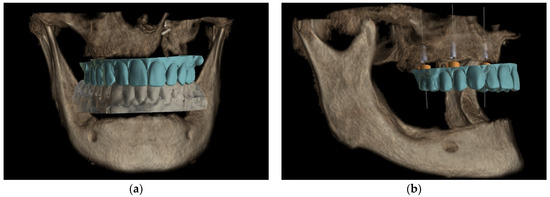

Maxilla-Oriented Implantology 多数歯欠損・無歯顎症例への。Prosthetically Driven Approach to Post-Ablative Maxilla。This patient previously underwent maxillectomy and free。多数歯欠損・無歯顎症例に特化したインプラント治療の専門書。。Rehabilitation of Maxillectomy Patients Using Zygoma。- タイトル: MAXILLA-ORIENTED IMPLANTOLOGY- 著者: 林 彦奈, 武田 孝之, 桜井 保幸, 森田 薫造- 内容: 多数歯欠損・無歯顎症例のインプラント治療- 定価: 22000円ご覧いただきありがとうございます。❤️❤️❤️❤️補綴の診断と予後❤️❤️❤️❤️役に立つ臨床ヒントと反省